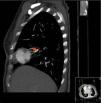

A contrast-enhanced computed tomography scan of the chest showed a pulmonary artery pseudoaneurysm with a maximum diameter of 45 mm at the right middle lobe, which was enhanced by contrast (Figure 1A and B). Pulmonary angiography confirmed the diagnosis (Figure 2A). After consultations with the respiratory medicine and interventional radiology departments, a percutaneous stent graft implantation was planned, in which a 6F multipurpose guiding catheter (Cordis) was placed and a PT2TM guide wire was positioned distal to the aneurysm. Under angiographic control a 3.5 mm×18 mm stent (BeGraft Peripheral Stent Graft System, Bentley Innomed) was placed in the pulmonary artery. This procedure was successful and there were no complications (Figures 2B and C).

Pulmonary angiogram confirming the presence and location of the pulmonary artery pseudoaneurysm (arrow), showing its extent: (A) anteroposterior view, with stent graft implantation (arrow) to treat the pseudoaneurysm; (B) anteroposterior view, showing an excellent result with unrestricted blood flow into the periphery when the bleeding had stopped (arrow); (C) anteroposterior view.